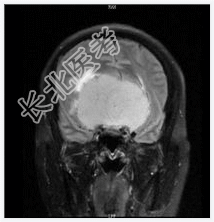

- [材料题] 患者女,55岁,视力下降数月。查体:视力下降,余神经体征阴性。

- 简答题1、诊断及依据是什么?

- 简答题2、鉴别诊断有什么?